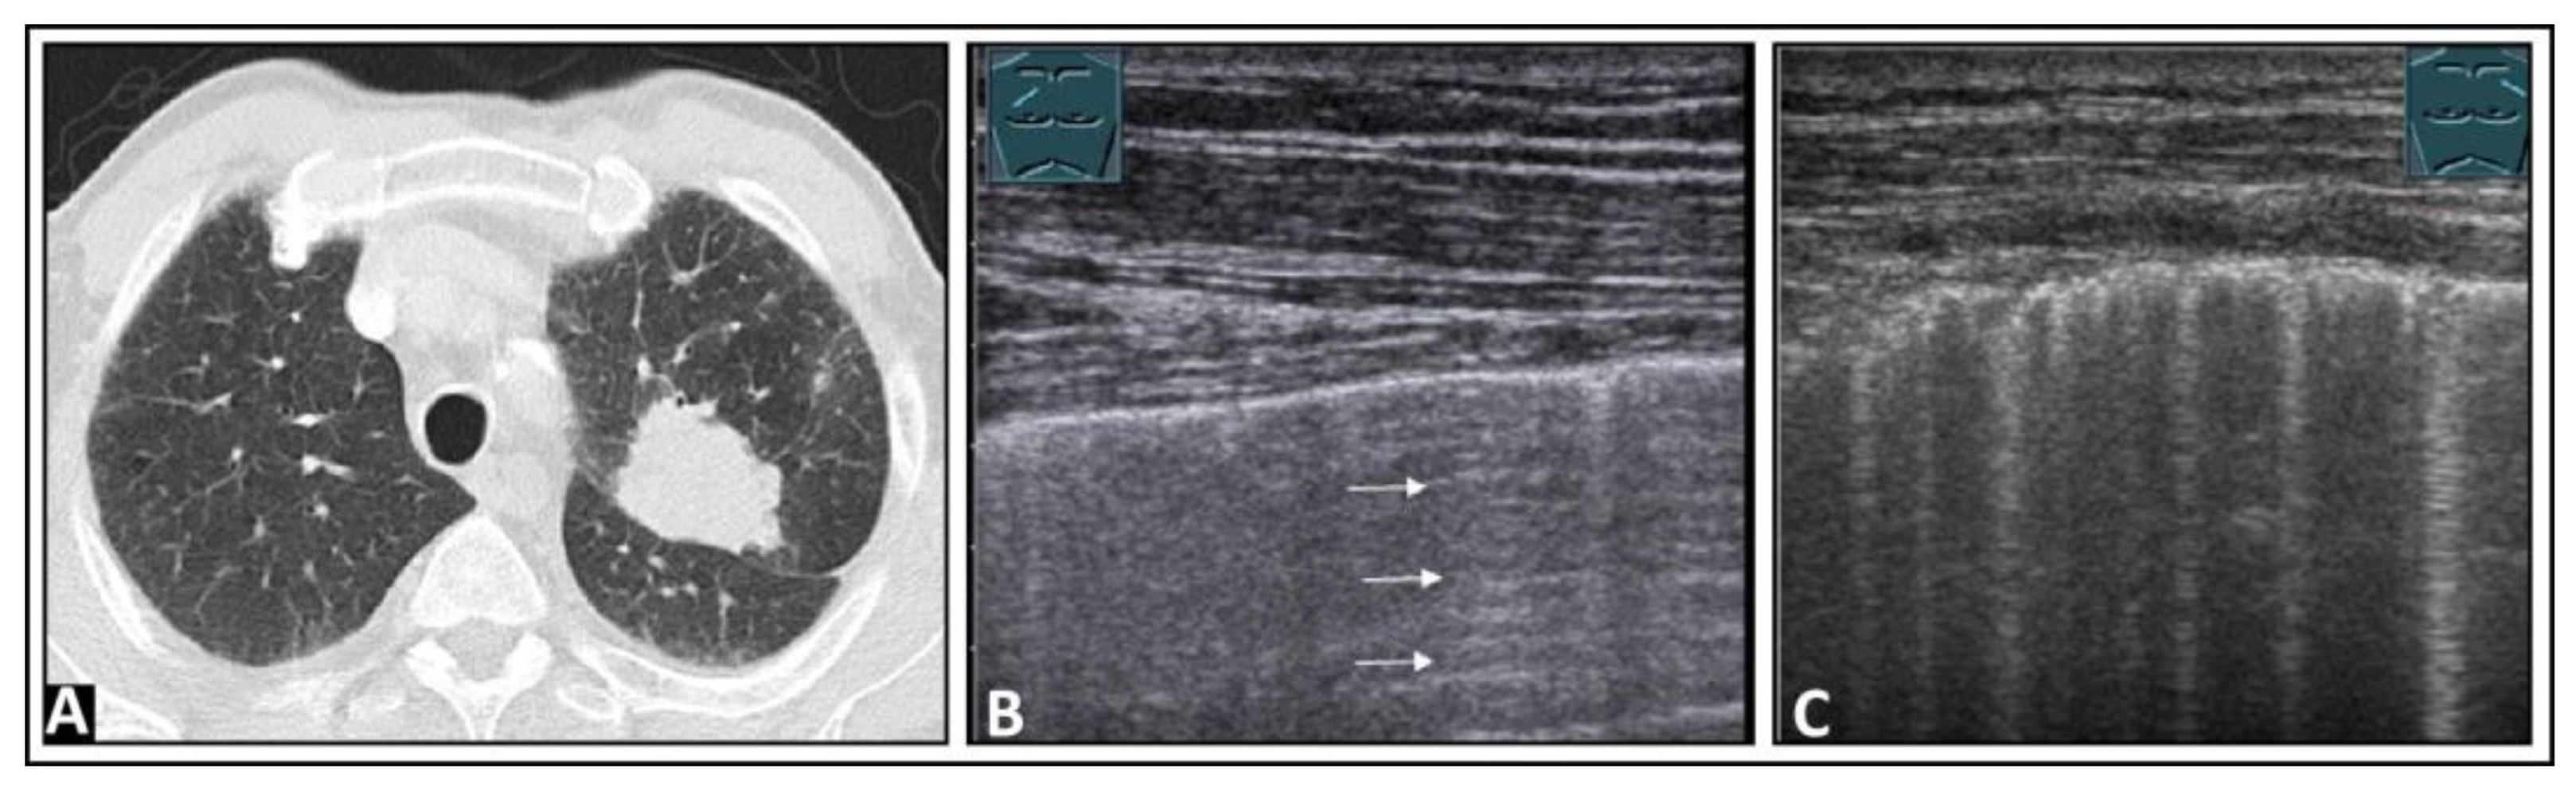

5. Pneumonia